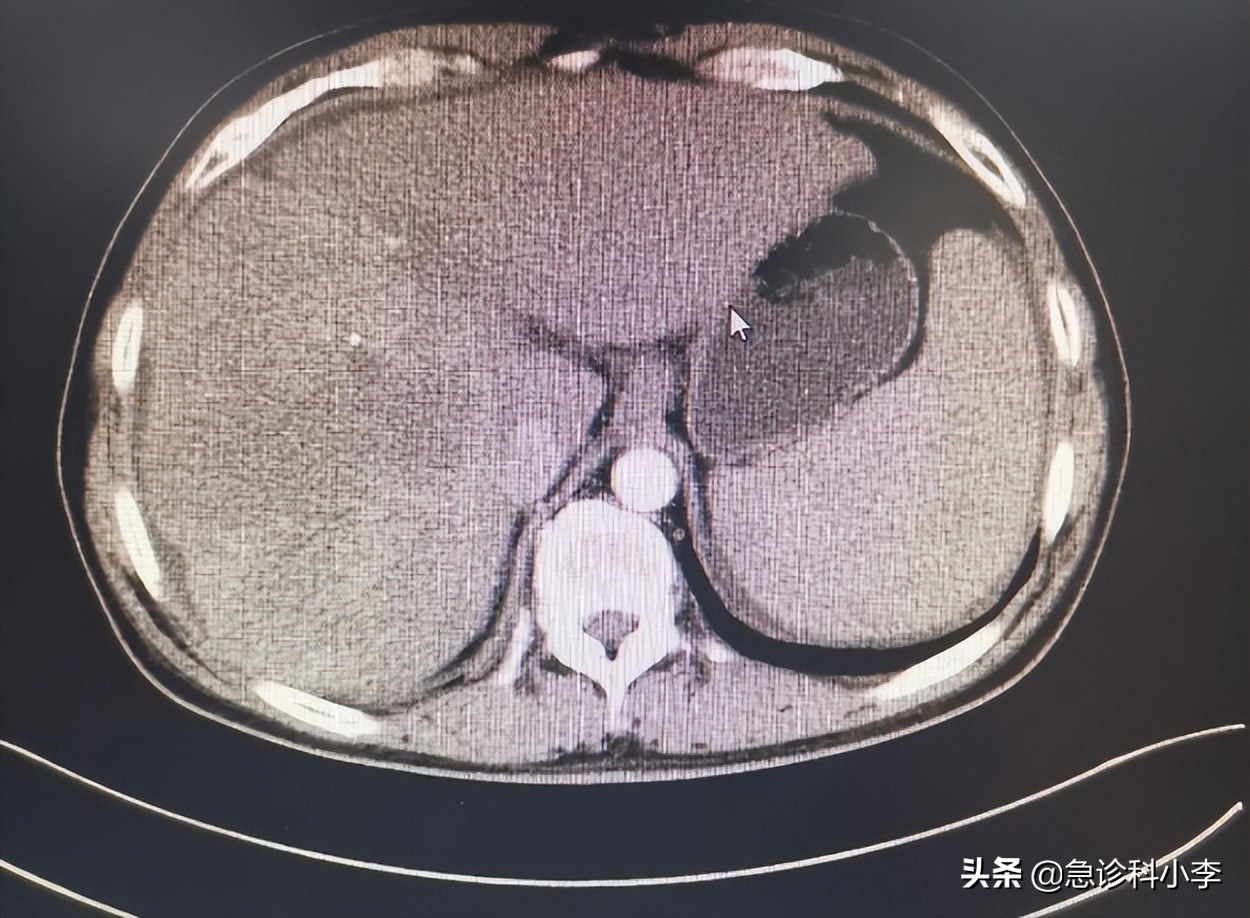

随后李先生做了抽血检验和腹部CT平扫,结果显示:血淀粉酶485U/L,腹部CT平扫可见胰腺轻度肿大,无出血坏死,胰腺周围明显渗出。可诊断为急性水肿性胰腺炎。

然而李先生的腹部CT平扫结果还提示其肝脏出现占位,无法明确是肝癌还是其他肝脏病变。要确诊只能等急性胰腺炎痊愈后,再进行增强CT扫描。